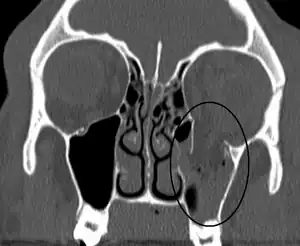

| An orbital blowout fracture of the floor of the left orbit. | |

Thin cut (2-3mm) CT scan with axial and coronal view is the optimal study of choice for orbital fractures.[14][15]